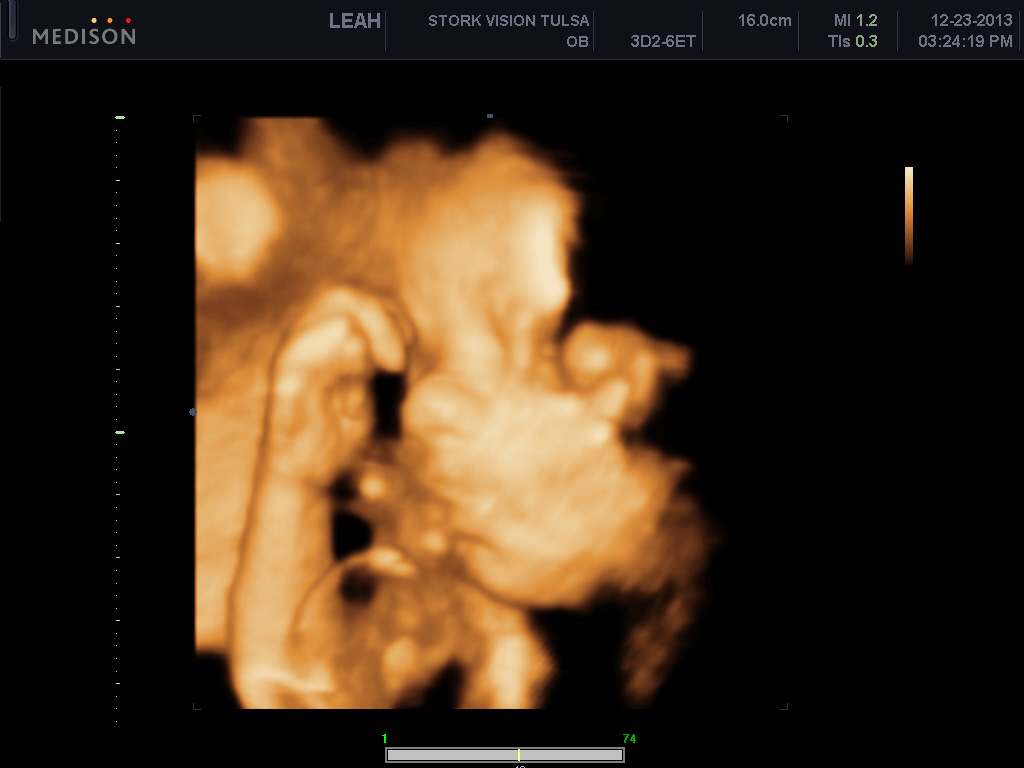

He's freaking adorable! These are my favs out of about 70 pictures..

Look at those cheeks!